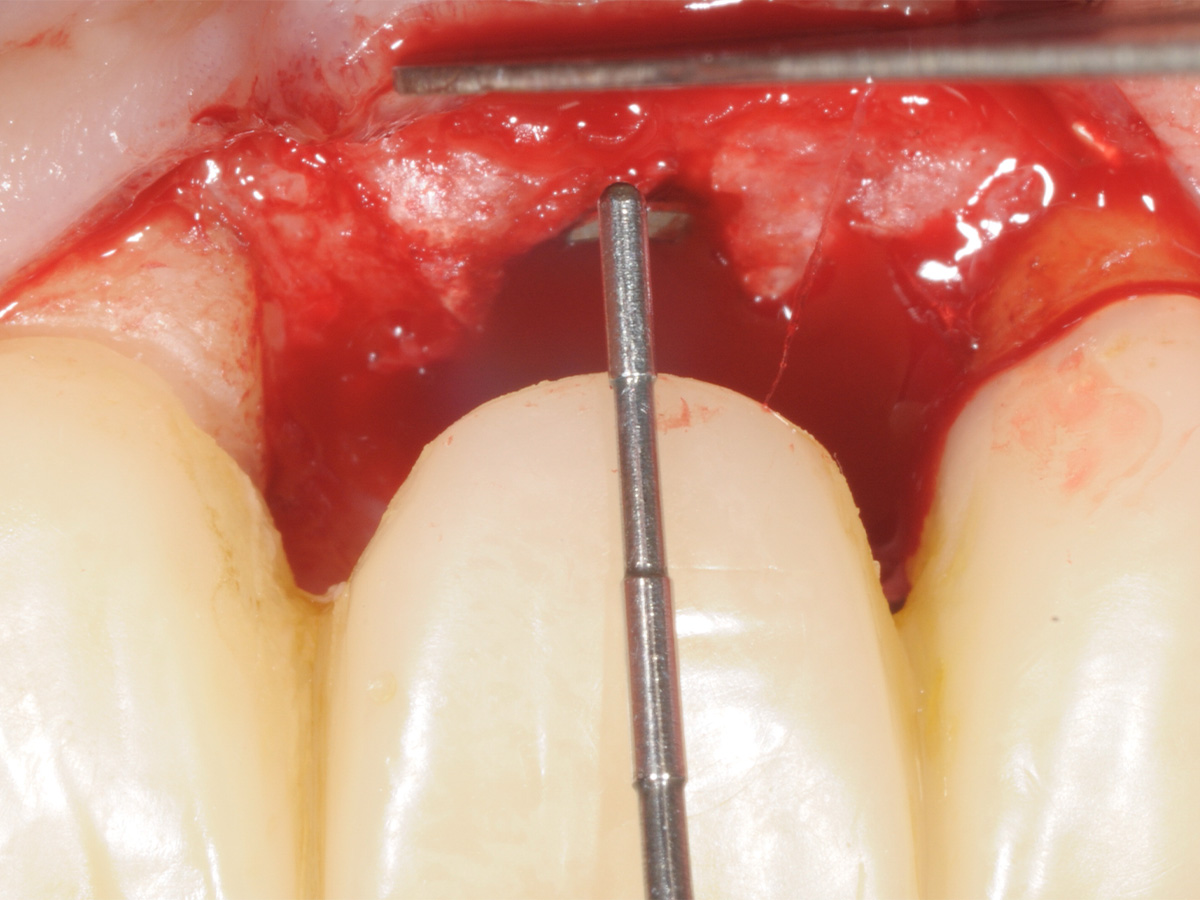

Abbildung 12

Implantation: Gutes Knochenvolumen in horizontaler und vertikaler Dimension.

Abbildung 13

Implantation in optimaler prothetischer Ausrichtung möglich, da ausreichendes knöchernes Angebot in vertikaler und horizontaler Dimension.